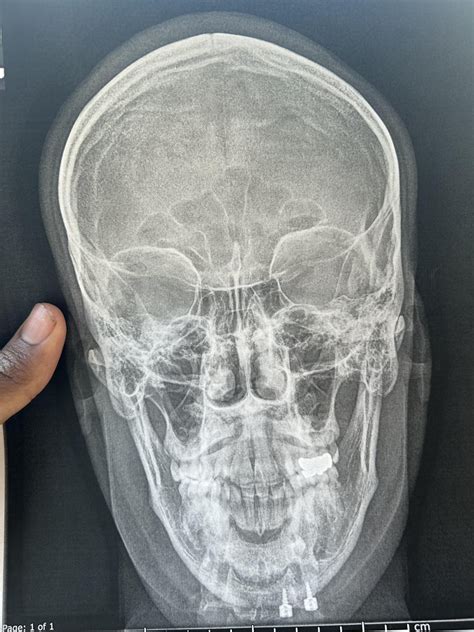

• Anatomical factors: Certain physical characteristics, such as a large tongue, small jaw, or enlarged tonsils, can contribute to airway obstruction.

• Nasal congestion: Conditions that block the nasal passages, such as allergies or a deviated septum, can force mouth breathing and increase the risk of sleep apnea.

• Tonsillectomy or adenoidectomy: Removal of enlarged tonsils or adenoids can improve airflow.

• Uvulopalatopharyngoplasty (UPPP): This procedure involves removing excess tissue from the throat to widen the airway.

• Jaw surgery: In some cases, surgery to reposition the jaw can help alleviate sleep apnea.